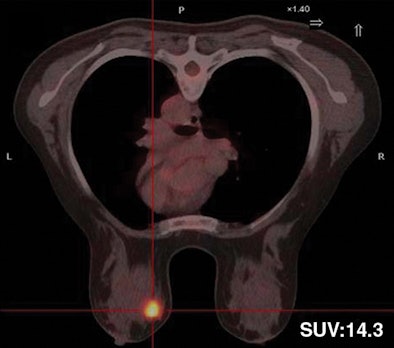

| Thirty-two-year-old woman with ductal infiltrating adenocarcinoma measuring 18 mm in maximum transverse diameter. Axial fused PET/CT images obtained with patient in prone position at time point 1 (above) and time point 2 (below) show corresponding standard uptake values. |

| Above, subtracted contrast-enhanced T1-weighted axial MR image shows focal area of intense F-18 FDG uptake and marked gadolinium enhancement in superior inner quadrant of right breast. |